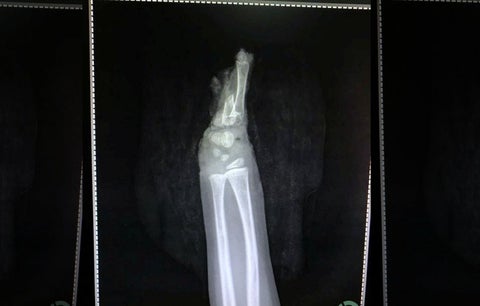

La medicina logró completar un nuevo reto cuando la mano de un niño fue unida a su muñeca, luego de que la misma fuera mutilada con un cortacésped.

El pequeño de cuatro años y originario de la India, estaba jugando con el aparato eléctrico que suele usar su padre, cuando accidentalmente su mano izquierda quedó atrapada en la maquina siendo amputada completamente.

"Su mano izquierda estaba completamente cortada con parte de los huesos unidos al cuerpo mientras la piel y el músculo de dicha extremidad se desprendían", dijo el Dr. Abhishek Ghosha, un cirujano microvascular que trató al niño.

El menor fue sometido a una cirugía que duró seis horas, en la que los especialistas utilizaron injertos de piel y venas de una de las piernas del infante. “Al ver la corta edad del niño, se decidió intentar salvar la mano. El paciente fue llevado a cirugía inmediatamente después de llegar al hospital y se le administró anestesia", narró el galeno a los medios locales.

La mano amputada se observó de cerca bajo el microscopio y se notó un pequeño vaso sanguíneo dentro del músculo. Luego, este pequeño vaso se unió a la arteria principal del antebrazo con la ayuda de un largo injerto de vena tomado de la pierna”, continuó. "Comenzó la circulación de la mano y las venas se unieron minuciosamente".

El niño permaneció en el hospital durante una semana después de su cirugía. Pronto comenzará la fisioterapia para recuperar la función normal de su mano izquierda.